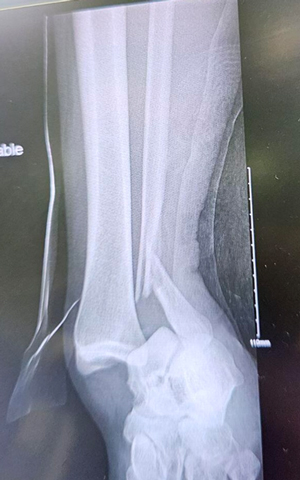

TOTAL ANKLE REPLACEMENT :: ORIF CALCANEUS :: ORIF ANKLE FRACTURE DISLOCATION :: COMPLEX BUNION AND LESSER TOE CORRECTION :: TALUS FRACTURE -1 :: TALUS FRACTURE -2 :: LISFRANC REPAIR :: COMPLEX TRIPLE ARTHRODESIS 1 :: COMPLEX TRIPLE ARTHRODESIS 2 :: MINIMALLY INVASIVE BUNION REPAIR 1 :: MINIMALLY INVASIVE BUNION REPAIR 2 :: ARTHROSCOPIC CARTILAGE REPAIR :: TENEX SPUR DEBRIDEMENT :: Haglunds Debridement and Achilles Repair